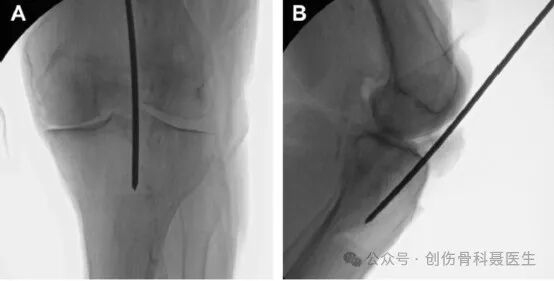

切口入点:正位位于胫骨机械轴与胫骨平台的交点,即胫骨外侧髁间棘的内侧缘,侧位位于胫骨平台与胫骨干移行区的分水岭上

标准的正位X片:正位X片的机械轴做一直线,在胫骨平台外侧缘做机械轴的平行线,该平行线在正位片上要平分腓骨头

标准的侧位X片,股骨内外侧髁基本重叠,内外侧胫骨平台基本重叠,侧位片上,进针点位于平台与胫骨干的分水岭